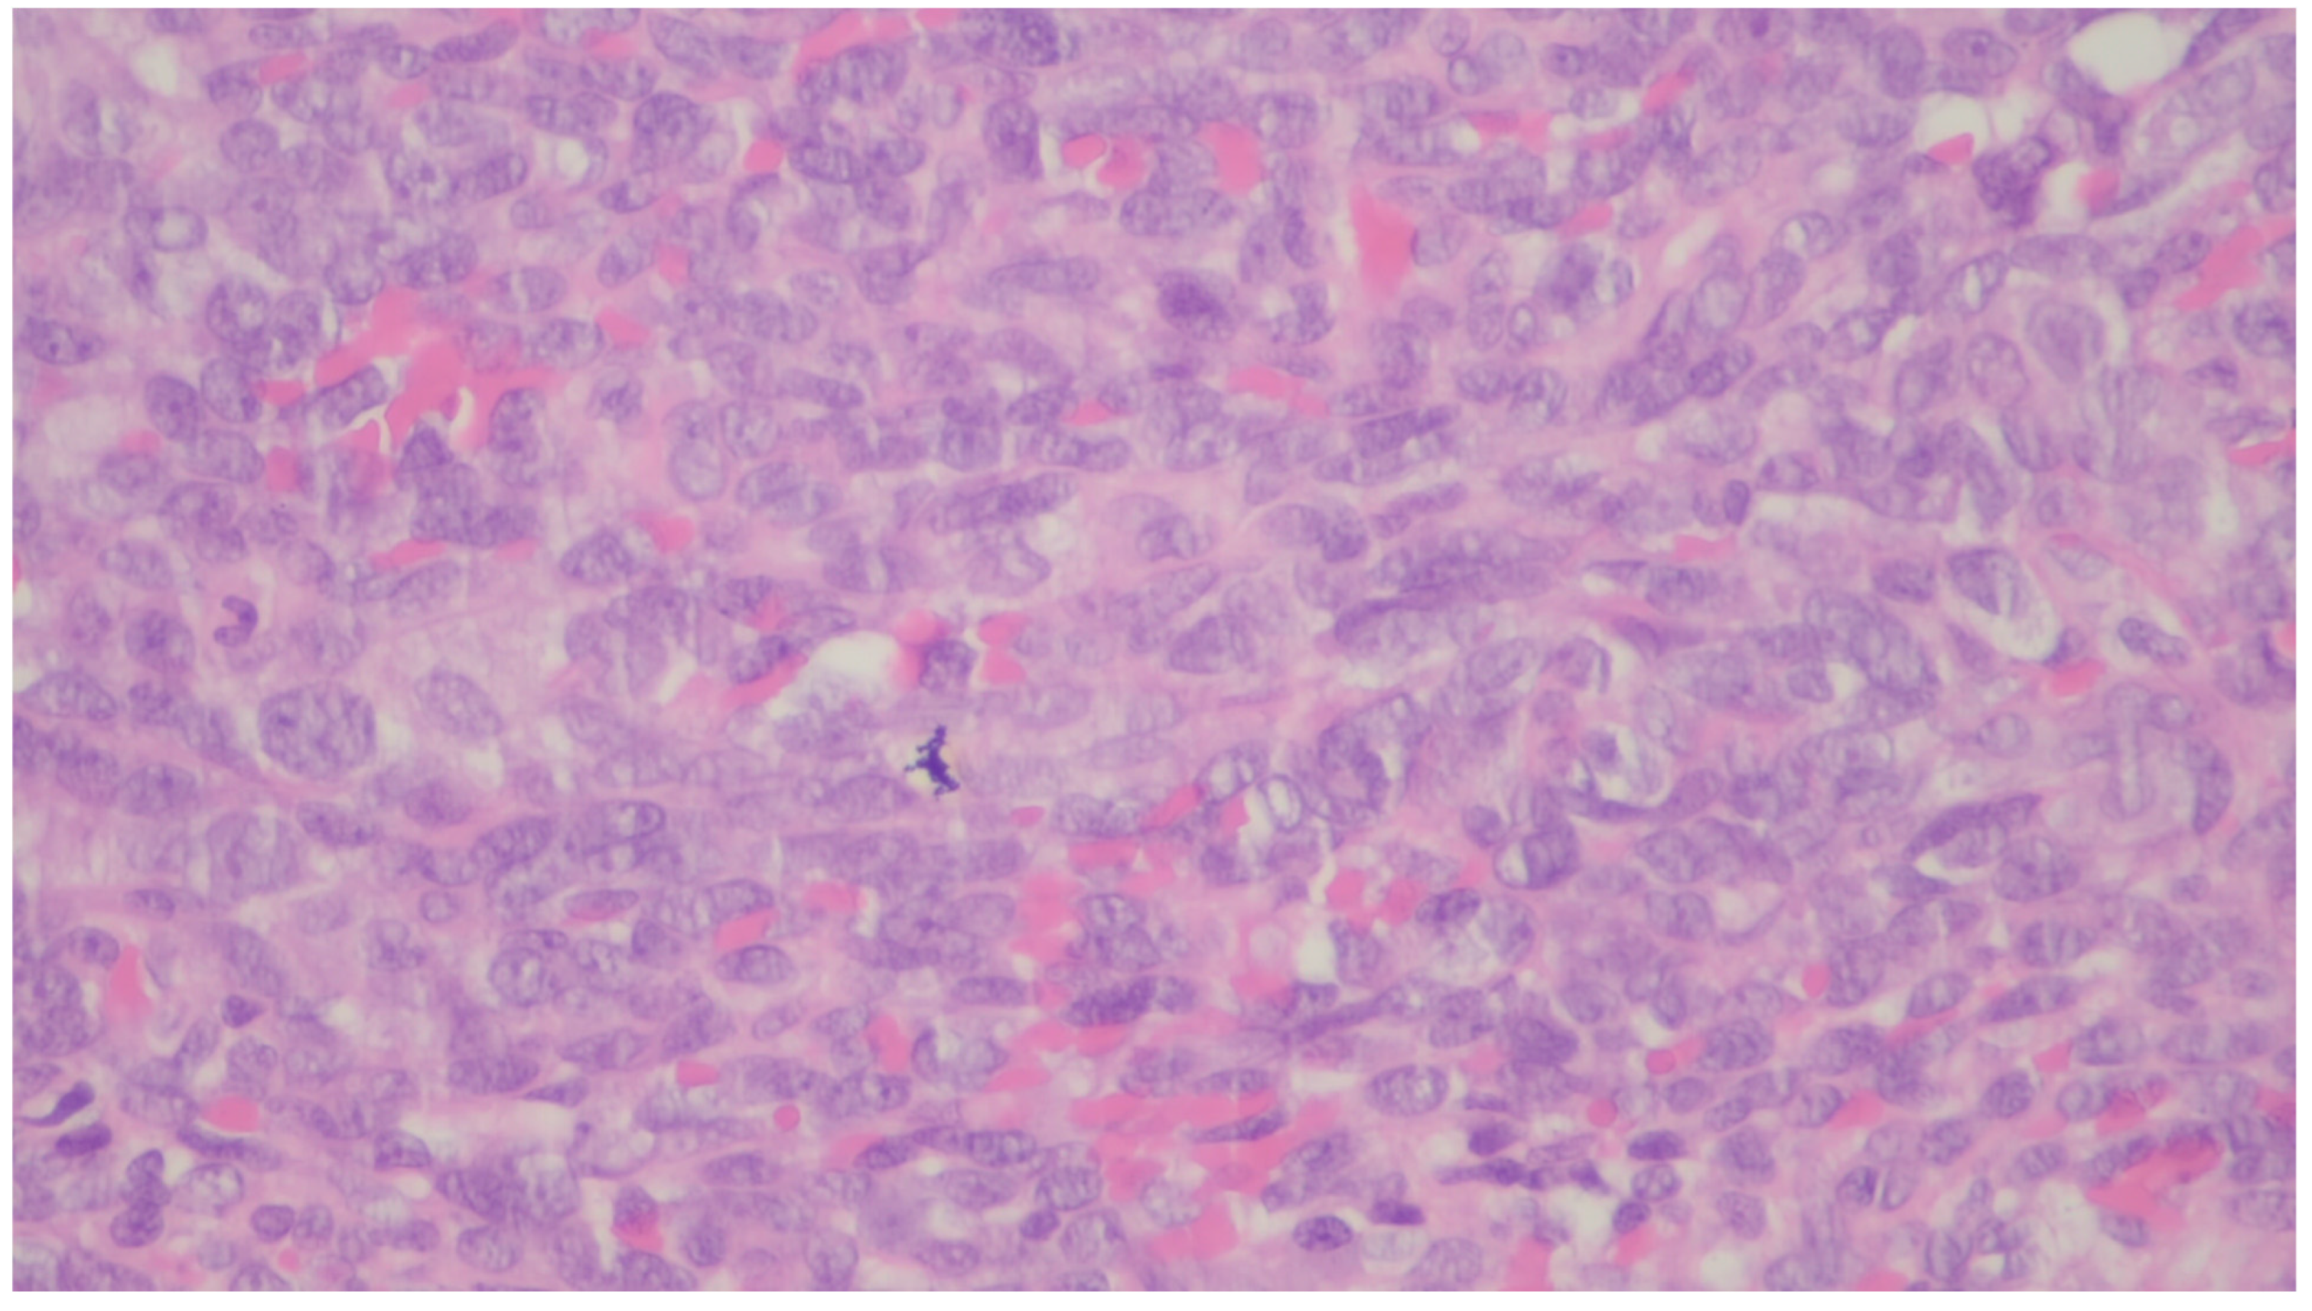

| NUTM1-rearranged colorectal sarcoma | Teens and young adults; more common in females | Colorectal | Symptoms are not specific | Three distinctive patterns: intersecting fascicles with uniform cells pattern, a hyalinized/nested pattern, and an epithelioid and rhabdoid pattern | nuclear expression of NUT, variable keratin expression and expression of CD117 and DOG1, retained expression of SMARCB1 and SMARCA4 |